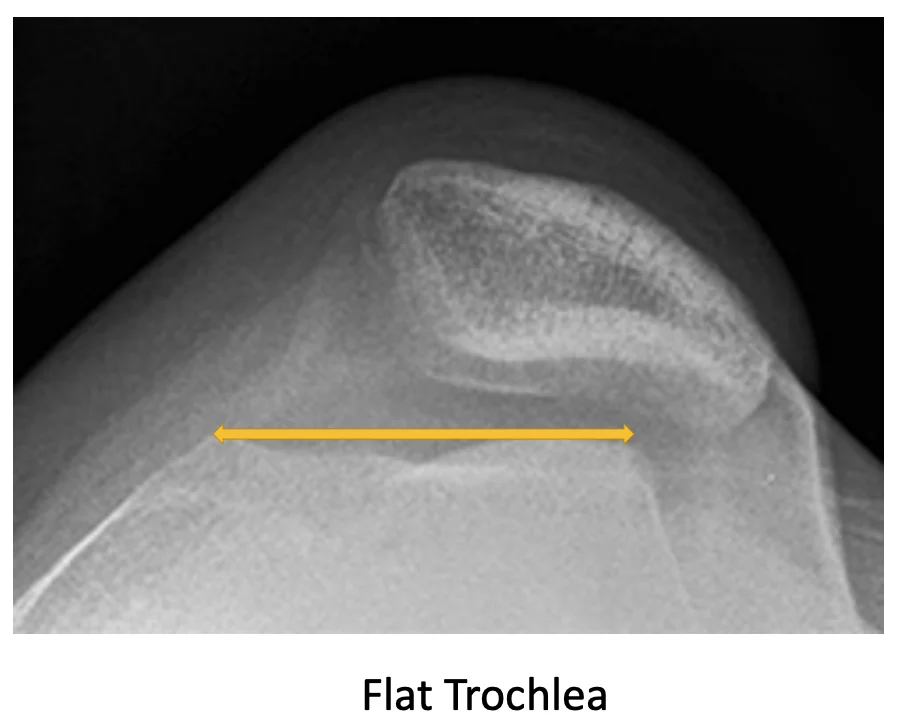

Key anatomical contributors include:

In cases where conservative methods including muscle strengthening had failed to prevent Patella to dislocate then after proper planning and investigations including MRI knee joint and special knee x-rays to evaluate underlying cause should be done before going for right surgery.